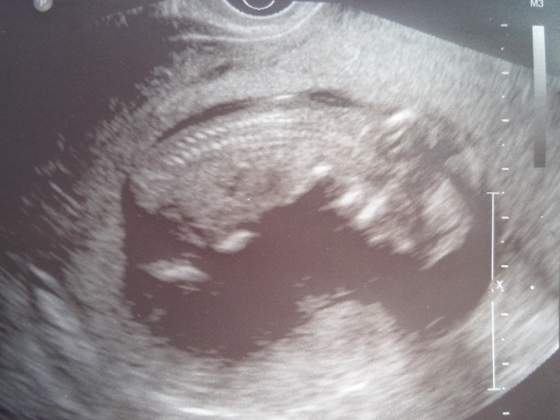

jejc.. jakie cudowne te zdjęcia